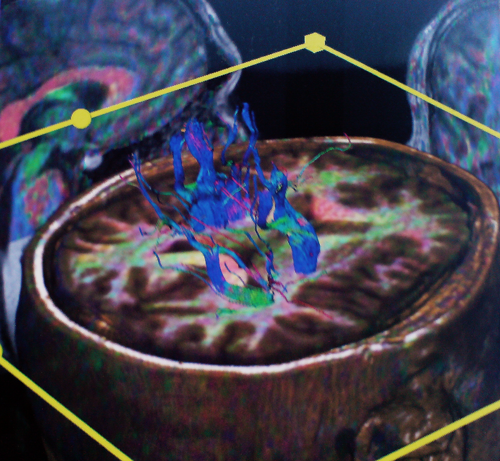

Navi13

Νευροπλοήγηση σε ασθενή με όγκο εγκεφάλου. Όγκος με πράσινο, αγγεία με κόκκινο και μπλέ, μετωπιαίος κόλπος με γαλάζιο.